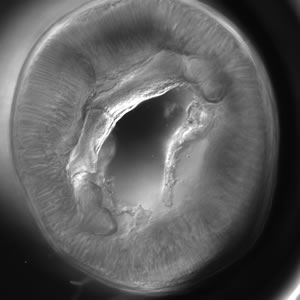

Anterior end of Pseudoterranova sp. The red arrow indicates the intestinal cecum.

Genus-level identification is not required for patient management but may be accomplished by examination of digestive structures and lateral chords. Examination of esophageal and intestinal morphology usually requires clearing in lactophenol.